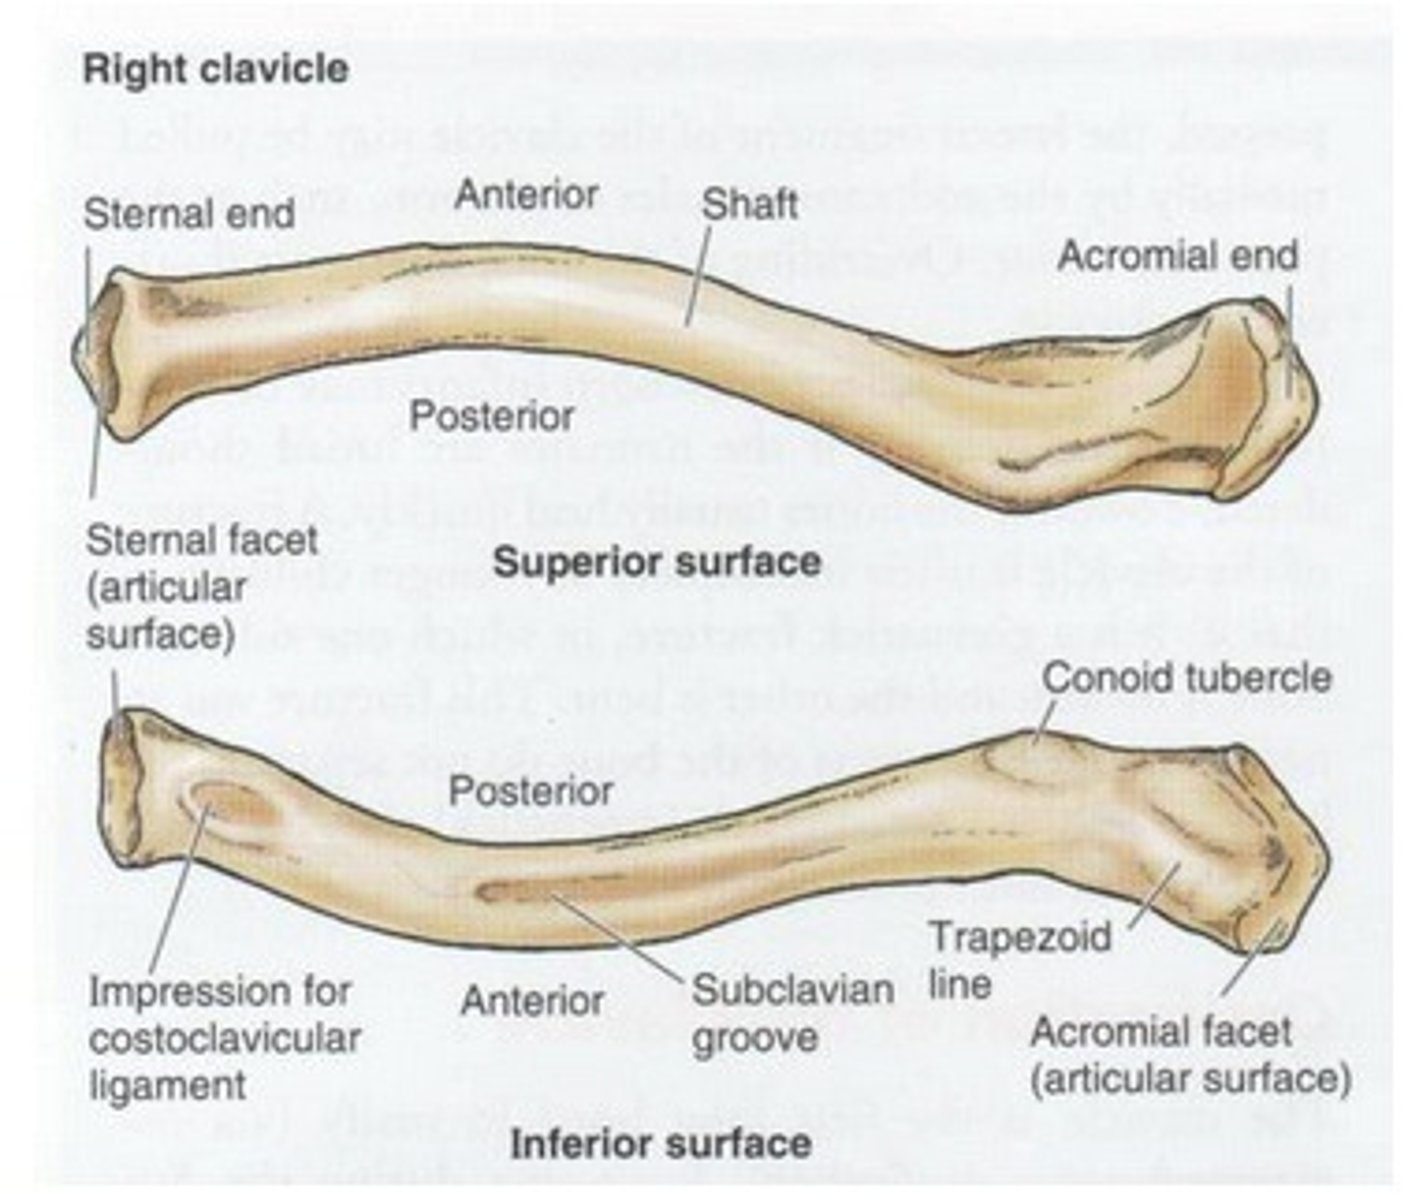

Parts of the clavicle:

- shaft

- superior surface

- inferior surface

Shaft of the clavicle:

double curved in the horizontal plane, which increases resilience

Middle half of the shaft of the clavicle:

convex anteriorly, and lateral half concave anteriorly

Sternal end of the shaft of the clavicle articulates:

articulates with manubrium via the sternoclavicular joint

Acromial end of the shaft of the clavicle articulates:

articulates with acromion via acromioclavicular joint

Location of superior surface of the clavicle:

lies deep to the platysma muscle and skin and it is smooth

Inferior surface of the clavicle:

rough surface with ligaments binding to it

Location of conoid tubercle of the inferior surface of the clavicle:

near acromial end of clavicle

Function of conoid tubercle on the inferior surface of the clavicle:

support for the medial part of the coracoclavicular ligament

Location of the trapezoid line of the inferior surface of the clavicle:

nearer to the acromial end than the conoid tubercle

Function of the trapezoid line of the inferior surface of the clavicle:

support for the lateral part of the coracoclavicular joint

Clinical relevance: fracture of the clavicle

Inflection point: The junction between the medial 2/3rd and lateral 1/3rd. The inflection point is the weakest point of the clavicle, more prone to fractures. The medial 2/3rd is going to be displaced superiorly by the action of the SCM (sternocleidomastoid) muscle